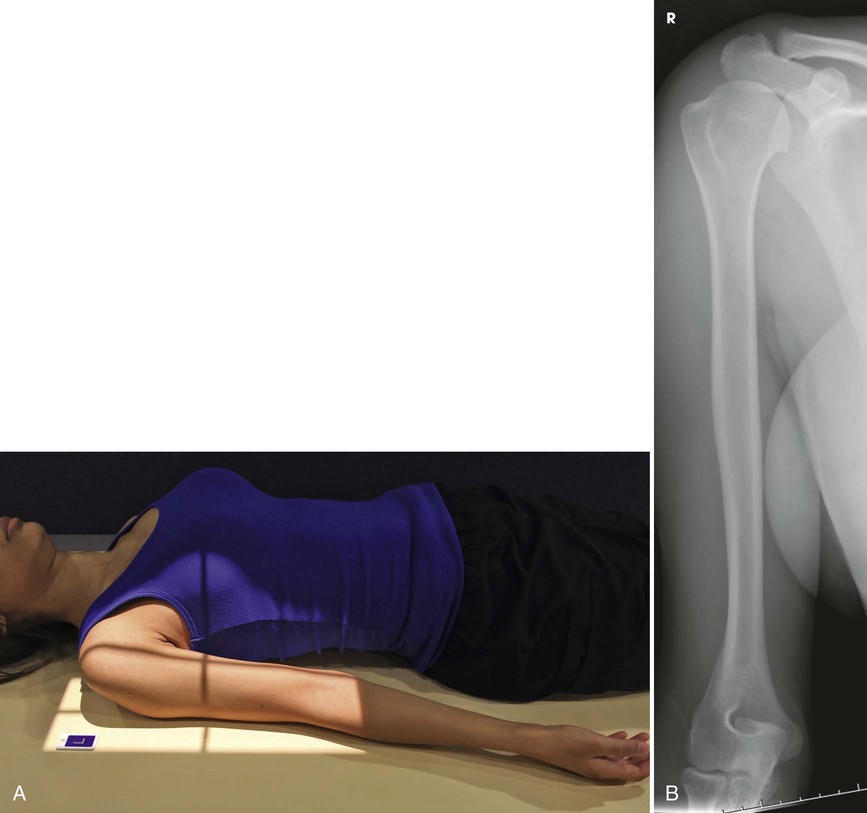

Position of part

• Place the upper margin of the IR approximately

inches (3.8 cm) above the humeral head.

• Elevate the opposite shoulder on a sandbag to place the affected arm in contact with the IR, or elevate the arm and IR on sandbags.

• Unless contraindicated, supinate the hand, extend the elbow, and rotate the limb to place the epicondyles parallel with the plane of the IR (Fig. 4-156).

Structures shown

The AP projection shows the entire length of the humerus. The accuracy of the position is shown by the epicondyles (see Fig. 4-156).